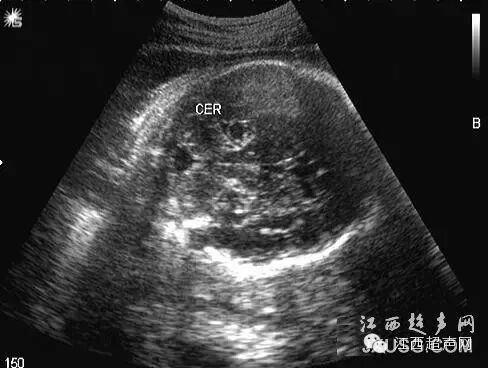

60.晚孕期的可见到第三脑室扩张,小脑下蚓部裂隙样声像,颅后窝池增宽的现象:其实是因小脑局部的挤压的使得两个小脑半球之间就有了这条'裂隙',而不是Dandy-Walker变异型,再者可能BPD平面左右半球打得不对称而出现的第三脑室的扩张。所以我们平时的一些正常解剖结构在特定时期,特定的条件下时的'变异声像'要有所了解,再者切面一定要标准.同仁们,小心落,陷阱!!!

彩超伪像是什么60个超声诊断中容易误诊的正常结构_https://www.jmylbn.com_新闻资讯_第14张